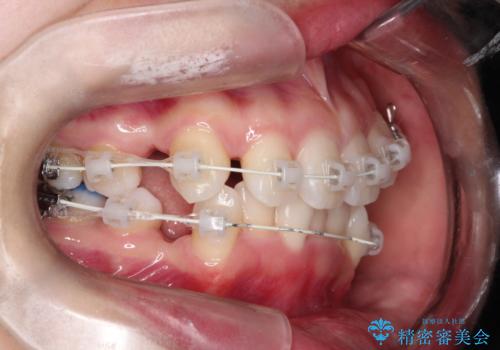

【審美ワイヤー】八重歯を治したい。

- 矯正装置

- 審美装置

- 左上の犬歯の凸凹や正中のずれを主訴に来院されました。

凸凹を治すために、上下左右の小臼歯を抜歯してワイヤー矯正を行いました。

患者様には、顎間ゴムを使用していただくことで、2年という期間で治療を終了することができました。